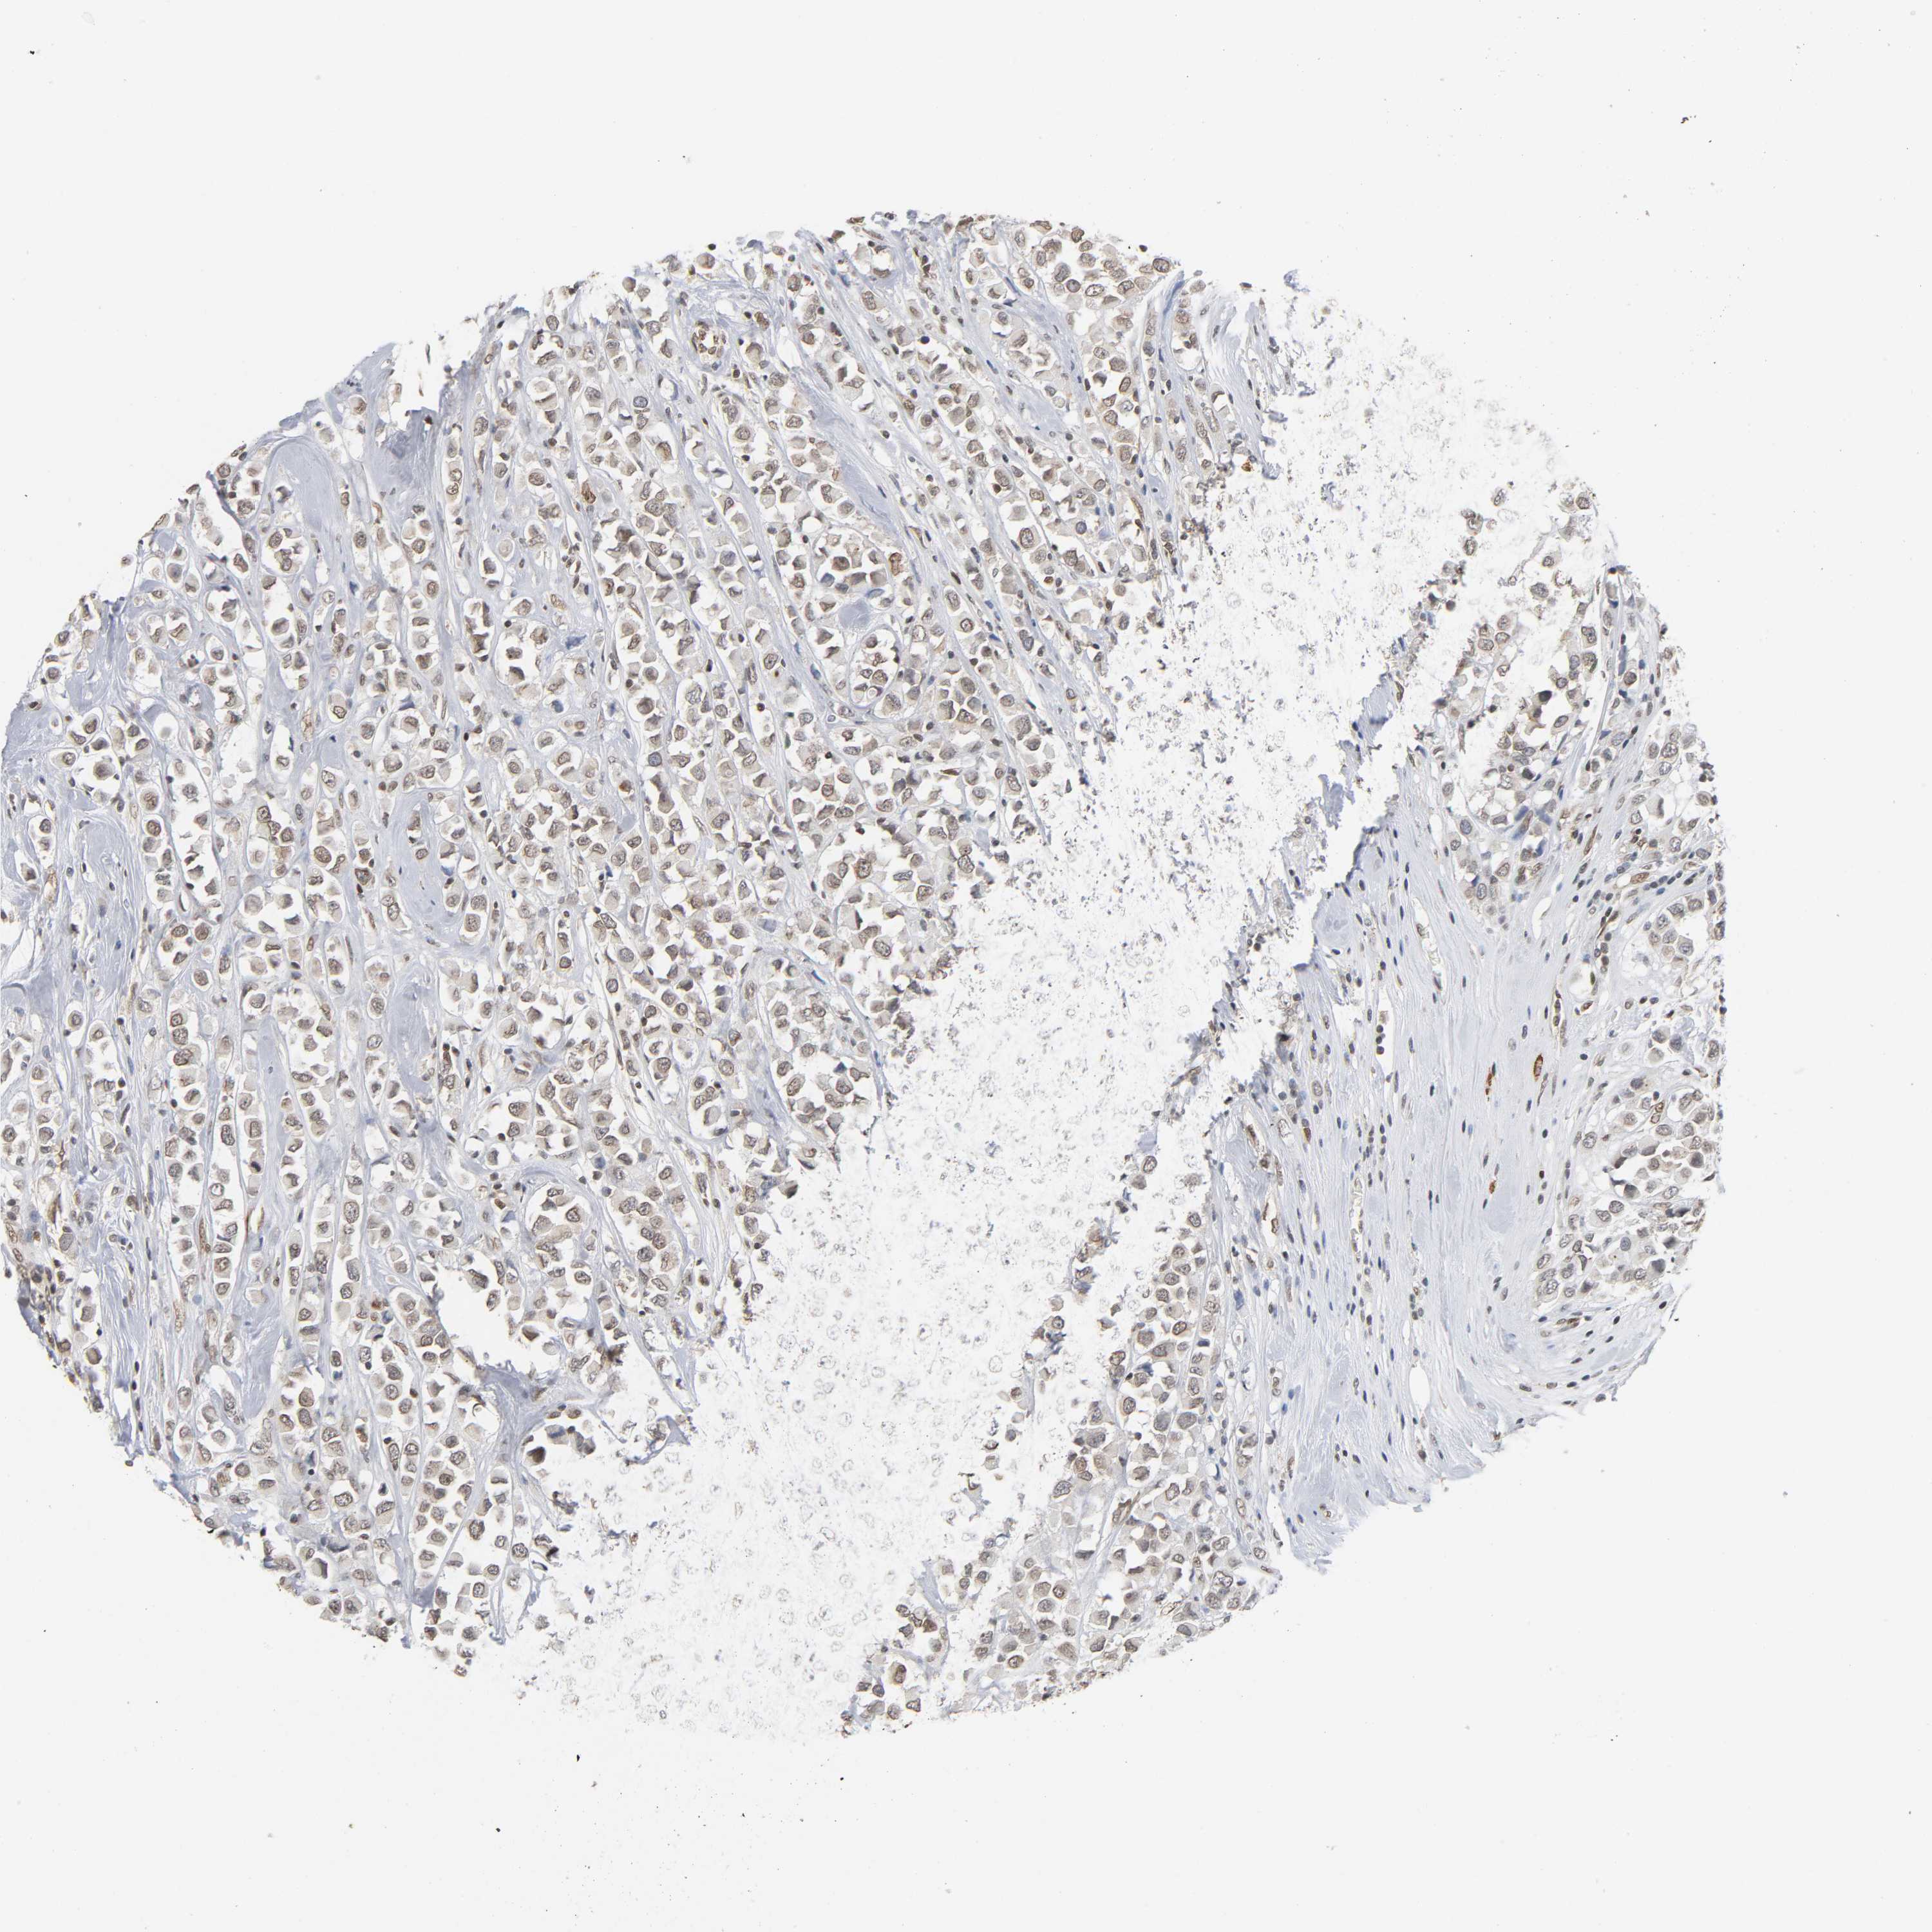

Breast cancer

Human cancer